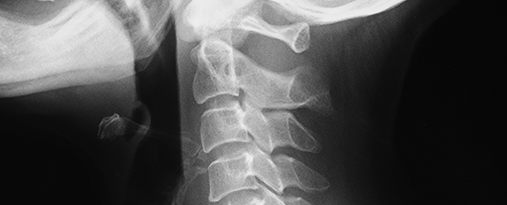

자기장을 이용하여 병변 부위를 관찰합니다.

근골격계의 움직임을 영상으로 촬영하여 측정합니다.